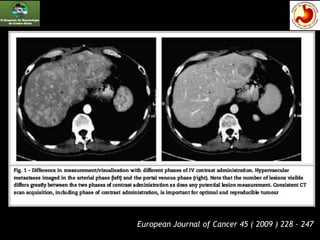

Tomografia Computadorizada

e Ressonância Magnética

 O uso de contraste é indicado com estudo trifásico

para lesões neuroendócrinas e para o

hepatocarcinoma.

 Idealmente, devem-se usar cortes com 5 mm ou menos

 Se apenas cortes mais grossos são disponíveis, o mínimo

tamanho da lesão para ser ALVO será o dobro da

espessura do corte.

European Journal of Cancer 45 ( 2009 ) 228 - 247